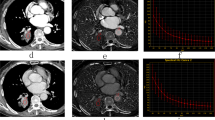

(a–c) Axial GSI monochromatic images in portal phase: (a,b) lung window images on different slices, (c) color-scale monochromatic images. (d) transverse fused images of PET/CT, (e) gross specimen, (f) histological section. Transverse GSI images demonstrated small circular lesions in the bilateral lower lungs. (a,b) showed the maximum cross section of the two lesions, respectively. (c) further demonstrated the mild enhancement within the lesions. (d) depicted circular lesions with slight FDG uptake in the relevant location. The SUVmax values were 0.22 and 0.36, respectively. (e) demonstrated metastasis in right lower lung clearly, further certified by histological section (f). Arrows pointed out the metastatic nodules.

Similarly, C-2 to C-7 [C3 shown in Supplementary Fig. 1] did not show any obvious positive performance with PET/CT and spectral CT [Fig. 3]. The SUVmax was approximately 0.3. However, radiological images of T-2 revealed one subcutaneous metastasis, which showed mild or moderate peripheral enhancement on DEsCT and much higher FDG uptake, with an SUVmax close to 1.2. The pathology-identified peritoneal tumours of T-2 were not differentiated from surrounding structures by DEsCT, whereas PET/CT coronal fused images depicted the focal abnormal uptake of metastases, with an SUVmax close to 0.98 [Fig. 4]. With successful peritoneal implantation, the results in the other mice (T-3 to T-7) were analogous to that of T-2, with SUVmax values of approximately 0.8, 1.06, 0.99, 0.83 and 0.96, respectively [T-3 to T-6 shown in Supplementary Figures 1,3,4 and 5]. A significant difference in the SUVmax of peritoneal metastasis was observed between the treated and control groups (P < 0.001).

(a–c) GSI monochromatic images in portal phase: (a) transverse monochromatic image, (b) transverse color-scale image, (c) coronal color-scale image. (d) coronal fused images of PET/CT, (e) gross specimen, (f) histological section. GSI images yielded excellent results of subcutaneous metastasis beyond the contour of abdomen, with peripheral enhancement confirmed by colour-scale image. PET/CT image depicted focal abnormal uptake of metastasis, including the peritoneal and subcutaneous ones. The corresponding SUVmax of subcutaneous and peritoneal metastasis were 1.2 and 0.98, respectively. (e,f) further illustrated a large number of peritoneal metastasis and huge subcutaneous metastasis shown on the GSI and PET/CT images. Arrows pointed out the peritoneal metastatic nodules, while arrow heads pointed out the subcutaneous metastasis.

Gross specimen analysis demonstrated a nodule in C-1 that was 0.8 mm in diameter [Fig. 1]. Two metastatic nodules in the T-1 gross specimen were 4.1 and 3.2 mm in diameter, respectively, which was consistent with findings using PET-CT images (4.27 mm and 3.45 mm, respectively). The lesion in the inferior lobe of right lung is shown in Fig. 2, whereas the other lesion on the left side was not visible in this image. C-2 to C-7 showed four to ten nodules on the peritoneum, with 3.1 mm being the largest in size by gross specimen. The average size of peritoneal nodules from C-2 to C-7 was 1.13 mm (ranging from 0.5 mm to 3.1 mm). T-2 to T-7 revealed 8 to 21 peritoneal lesions with 6.11 mm as the largest size confirmed by gross specimen (mean 2.66 mm, ranging from 0.6 mm to 6.11 mm). Additionally, T-2 showed another subcutaneous lesion, with 13.6 mm as the largest size. No significant difference in tumour number was shown between the treated and control groups (P = 0.528). For the peritoneal tumour size, there was a significant difference between the treated and control groups (P < 0.001). Therefore, the treated group showed an increasing average size of tumours in C-3 and other positive radiological images in T-3 to T-6 [see supplementary results].

Mice in the control group after successful implantation displayed no visible lesions, suspicious FDG uptake or enhancement. Compared with the control group, sFRP1 overexpression positively induced visibly larger nodules with increasing enhancement in lung metastasis and higher FDG uptake in peritoneal tumours. Simultaneously, subcutaneous metastases in the treated group showed positive functional performance both on DEsCT and PET/CT, i.e., increasing enhancement and FDG uptake, in addition to the visible size of the lesion. The SUVmax confirmed the increased FDG uptake. However, no obvious increased FDG uptake was identified in lung metastasis and no peritoneal tumours were differentiated in either control or treated groups by DEsCT. As verified by immunological and histological analysis, tumours from the treated group contained a greater number of proliferative cells, more microvessels and fewer apoptotic cells. Additionally, we demonstrated that sFRP1 contributed to in vitro angiogenesis and in vivo microvessel formation. Therefore, we argue that sFRP1 may contribute to positive performance in PET/CT and dual CT.

Angiogenesis plays critical roles in the growth of cancer36. Angiogenesis is related to increased perfusion, blood volume and permeability, leading to increased contrast enhancement, which indicates that the development of new vessels within tumours determines their performance on contrast enhanced CT. Put another way, the intensity of neovascularization determines the contrast enhancement37. The degree of enhancement in the corticomedullary phase has been shown to correlate with microvessel density, in terms of renal parenchymal neoplasm38. A similar result was found in a study of pancreatic carcinoma in which the level of CT enhancement depended on the MVD number39. The enhancement of lung nodules appears to be an indicator of vascularity as well40. Consistent with these previous studies, a sFRP1 up-regulation model (T-1) showed increased numbers of microvessels assayed by CD34 staining and demonstrated visibly abnormal CT enhancement compared with a control group (C-1), which showed no abnormal enhancement.

In view of the spatial resolution of 64-slice CT, we considered the increased tumour size may partly contribute to visible nodules with CT, especially for nodules in T-1 (4.27 mm and 3.45 mm for the average size, respectively), which were much larger than C-1 (0.8 mm). As a result, a subcutaneous tumour with a much larger size (13.6 mm) was visible and presented peripheral enhancement, compared to other invisible peritoneal tumours (1.6 mm for the average size) in T2 by DEsCT. With limited resolution, peritoneal tumours with insufficiently increasing size for visibility showed similar enhancement with the surrounding structures on DEsCT, which may contribute to the negative performance observed in T2 to T7. Tumour cell proliferation and angiogenesis were both considered to be necessary in the development of a detectable tumour32. Nevertheless, PET-CT provides functional imaging for tumours rather than mere morphology. Peritoneal nodules showed positive performance with higher SUVmax on PET/CT. The reason why the visible lung metastases from T-1, with a larger size, showed similar FDG uptake to those from C-1 in this study is currently unclear. We believe that size was not the determinant that changed the imaging appearance of tumours.